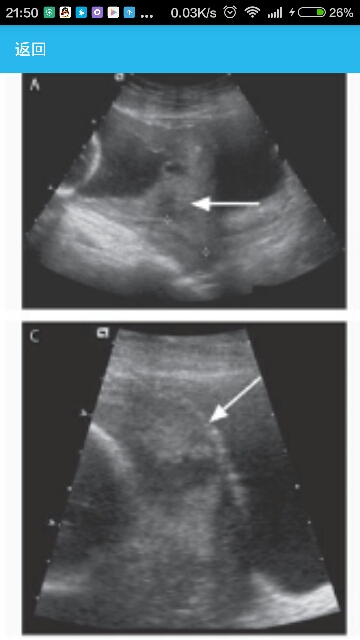

患者,女,40岁,妊娠22周零2天时因前置胎盘和侵入性胎盘就医。 病史从妊娠12周零1天开始,该患者曾在本医院的附属健康中心接受常规的产前保健。她孕5产4,并且她头两次妊娠曾有正常的足月阴道分娩,(分娩时间分别)在16年和9年前。7年前,该患者在足月时因产程中臀先露而被施以一次剖宫产术。由于胎儿难以取出,最初的子宫下段横切口被扩展为高位纵切口。该患者的血细胞比容曾由33.6%降至产后的17.6%(非妊娠妇女的参考值范围是36.0%~46.0%)。本次入院前5年,该患者在足月时被施以一次择期剖宫产术,并采用了(子宫)下段横切口的术式,产后的血细胞比容为28.9%。8年前针对结核病进行的一次皮试结果曾为阳性,以及一次胸部X线片检查结果正常,该患者曾被给予异烟肼治疗6个月。该患者有缺铁性贫血,为此医师曾开具铁补充剂的处方,但由于胃肠道不耐受而停止治疗。她曾有过水痘—带状疱疹病毒感染,并且风疹抗体筛查结果阳性。 临床表现在妊娠20周零6天时,重复进行的子宫超声检查显示一个有活力的单胎,以及一个右侧完全性前置胎盘,胎盘有大面积的无回声区,在邻近膀胱处子宫肌层的无回声带缺失,子宫前下段内的静脉结构和血流增多,这些特征均提示侵入性胎盘。宫颈长度>3 cm,没有形成漏斗,并且胎儿的解剖学结构、羊水量和脐带看起来均正常。在妊娠21周零2天时,该患者的体重是63.5 kg,血压80/64 mmHg,以及宫高符合妊娠21周(的标准)。胎心率为140次/分。 辅助检查在妊娠中、后期的常规胎儿超声检查期间,我们注意到了一个完全性前置胎盘(图 1A)。考虑到前置胎盘以及该患者既往的两次剖宫产术史,我们估计侵入性胎盘的危险大约为40%。然而,超声图还显示胎盘的间质内有大面积的无回声区(图 1B),胎盘下正常低回声子宫肌层带的缺失(图1C),以及子宫下段周围的血管供应增加(未显示)。加在一起,这些额外的检查所见提示侵入性胎盘的危险>60%。 诊断前置胎盘伴侵入性胎盘。 治疗该患者拒绝了自体献血和输血以及急性术前血液稀释的选择。她愿意接受铁治疗、药物刺激红细胞生成,以及只要自身输血回路仍与她的循环保持连续性,就采用一种细胞回收器系统进行自身输血。考虑到该患者出血的危险高、坚持不用血液制品以及由此导致的母亲死亡危险高,我们组建了一个多学科(治疗)小组,包括来自母—婴医疗服务部、血液科、社会服务机构、医院顾问、产科麻醉学、血管外科、泌尿外科、妇科肿瘤、输血医学、产科护理以及新生儿学的代表。 由于该患者不想再要孩子,预计将对其进行剖宫产子宫切除术(不尝试移除胎盘)。 手术在分娩之后,我们为球囊充气,并迅速关闭子宫。然后我们检查了骨盆,并且看上去胎盘组织出现在子宫之外,并向两边的骨盆侧壁延伸。在妇科肿瘤玛塞拉•戴尔•卡门医师的帮助下,我们实施了一次子宫切除术,一次性完整地切除了子宫、宫颈和胎盘。我们采用了数次8字缝线法以控制来自血管蒂的出血。球囊被放气后止血(效果)仍然持续。我们在用靛胭脂染色的生理盐水充盈膀胱后发现其仍然完好。我们以常规方式关闭切口。